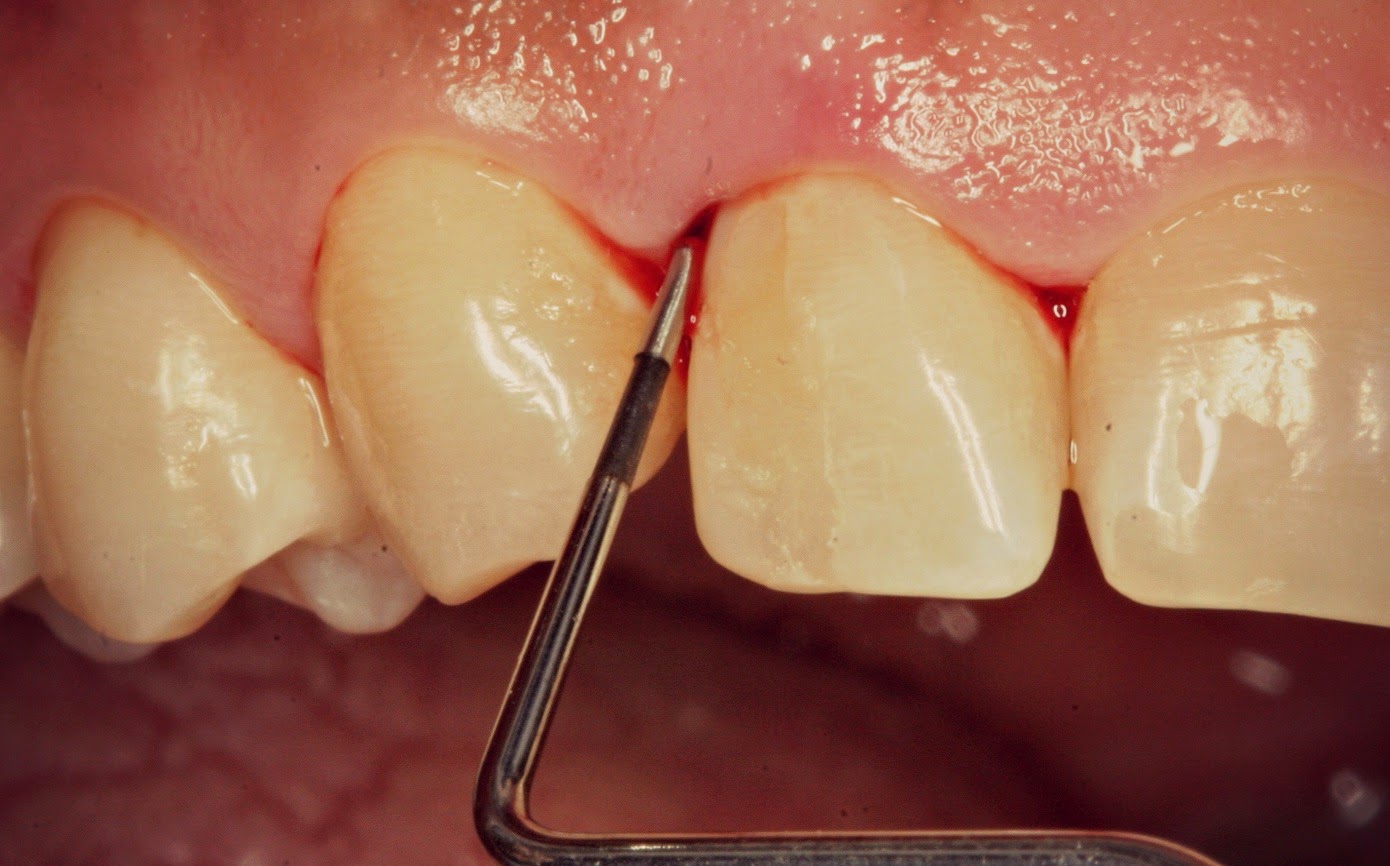

Bpe Probe Measurements . This has a ‘ball end’ 0.5mm in diameter and a black band from 3.5mm to. learn how to perform a bpe screen for all adult patients using a who bpe probe and a light probing force. The who bpe probe (left) has a 0.5 mm diameter ball end and a black band at 3.5 mm to 5.5. learn how to perform the basic periodontal examination (bpe) using a who bpe probe and record the results in the patient notes. a world health organisation (who) bpe probe is used. the bpe should be performed using the who 621 probe with a light probing force of between 20 and 25 grams.

a world health organisation (who) bpe probe is used. The who bpe probe (left) has a 0.5 mm diameter ball end and a black band at 3.5 mm to 5.5. learn how to perform the basic periodontal examination (bpe) using a who bpe probe and record the results in the patient notes. This has a ‘ball end’ 0.5mm in diameter and a black band from 3.5mm to. the bpe should be performed using the who 621 probe with a light probing force of between 20 and 25 grams. learn how to perform a bpe screen for all adult patients using a who bpe probe and a light probing force.